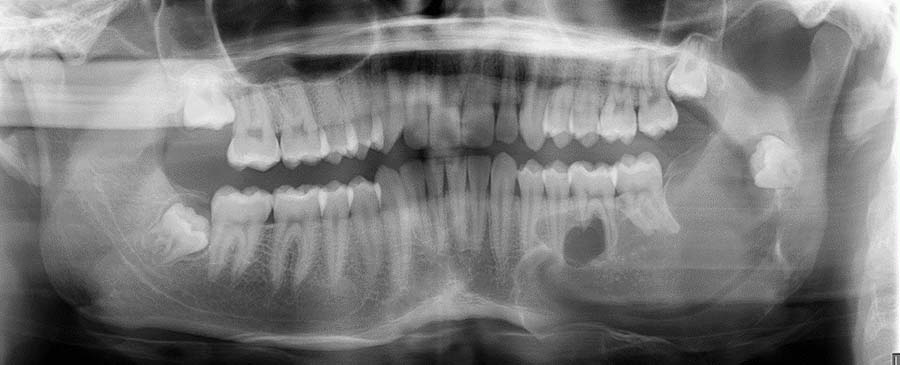

Oral & Maxillofacial Surgery

Compassionate care for every aspect of your face and oral health